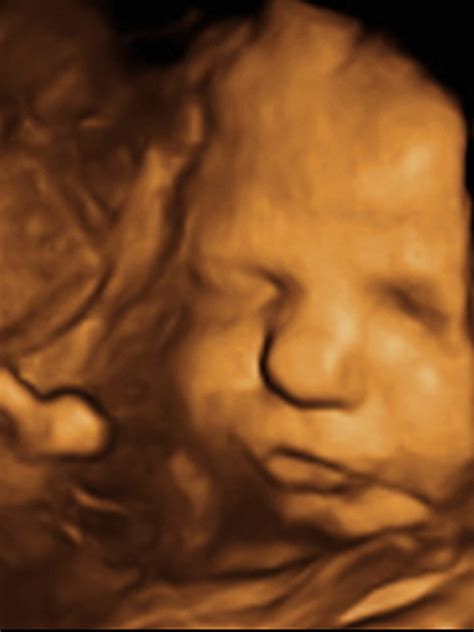

3D a 4D ultrazvuk

Ide o špeciálne zobrazenie bábätka, ktoré vidíte trojrozmerne (3D) a v reálnom čase (4D). Z takéhoto vyšetrenia vám lekár zvyčajne natočí video. Môžete vidieť tvárové črty vášho bábätka a dokonca zistiť, na koho sa podobá. Aj keď toto vyšetrenie má svoje limity, je medzi budúcimi mamami pomerne obľúbené a často vám lekár môže vytlačiť aj 3D fotografiu dieťatka. 3D-4D zobrazením môžeme lepšie posúdiť niektoré morfologické anomálie plodu.